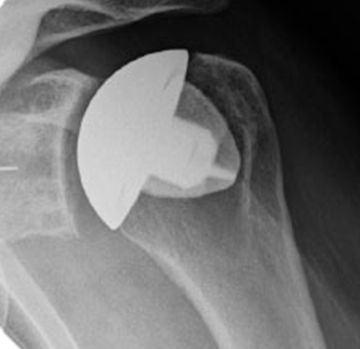

Anatomic Total Shoulder Replacement

If your rotator cuff tendons are in good condition, your surgeon may well recommend anatomic total shoulder replacement. In this procedure, your damaged joint surfaces are removed and ‘replicated’ with metal and plastic implants that are tailored to mimic your own anatomy.  Your rotator cuff tendons, which must be intact for this operation to function well, are preserved. The socket side on the shoulder blade is made of medical grade polyethylene (a special hard-wearing plastic) that is fixed into your bone using pegs and a small amount of bone cement.  The humeral side has a very highly polished surface and is made out of cobalt chrome (a hard-wearing metal alloy) or occasionally ceramic.  The humeral implant is either fixed using very short roughened fins that grip the bone in the upper arm bone (stemless), or by the use of a stem that grips inside the canal of your arm bone.

Anatomic total shoulder replacement  - metal 'stemless' humeral head and plastic socket (therefore not seen easily on Xray)